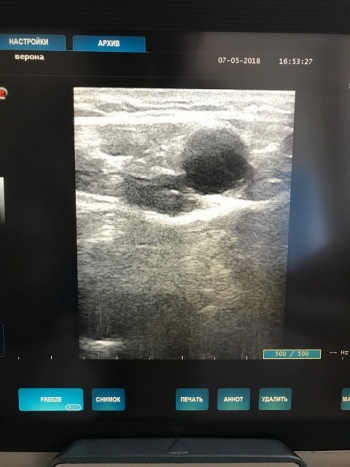

При выполнение ультразвукового дуплексного сканирования, выявлена несостоятельность остиальных клапанов и клапанов ствола больших подкожных вен, варикозные изменения притоков и несостоятельность перфорантных вен.

Фото: Ультразвуковая картина варикозно расширенной вены с выраженной клапанной несостоятельностью.